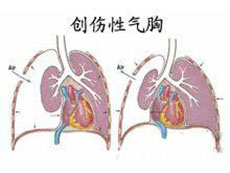

严重颅脑损伤、多发伤、复合伤

疾病介绍:严重颅脑损伤、多发伤、复合伤,多为交通、工矿事故、自然灾害、爆炸、火器伤、坠落、跌倒以及各种锐气、钝器对人体伤害。除正确诊断和及早手术外,加…【详细】